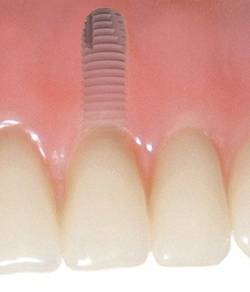

Zubní implantáty jsou umělé zubní kořeny.

Jsou zavedeny do kosti horní nebo dolní čelisti a umožňují náhradu jednoho, několika či všech zubů pomocí korunek, můstků, které jsou na ně připevněny nebo tvoří podporu pro zubní protézy.

BEGO Semados ® implantáty jsou vyrobeny z čistého titanu - materiálu, který je plně akceptováno v lidském těle, jejichž povrch má speciální úpravu

TiPurePlus pro bezpečnější, rychlejší a kvalitnější hojení.

Klasickým příkladem a indikací pro použití implantátu je ztráta jednoho zubu (v tomto případě v předním – frontálním úseku) v jinak zdravém, nepoškozeném chrupu.

Nejčastější příčinou takové ztráty je sportovní nebo dopravní úraz.

Náhrada jednoho zubu pomocí implantátu je možná také v postranním úseku chrupu. Při ztrátě většího počtu zubů ve frontálním nebo postranním úseku může být mezer uzavřena větším počtem jednotlivých implantátů.

Při ošetření pomocí jednotlivých implantátů zůstávají sousední zuby neporušené – intaktní. Při klasickém ošetření pomocí můstků musejí být tyto zuby obroušeny!